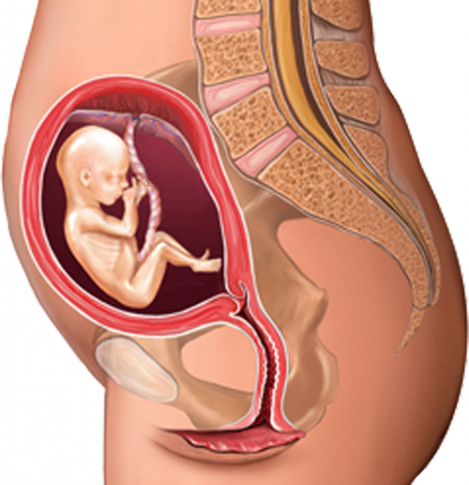

Физиология беременности: строение органов

Раздел: Моменты озарения